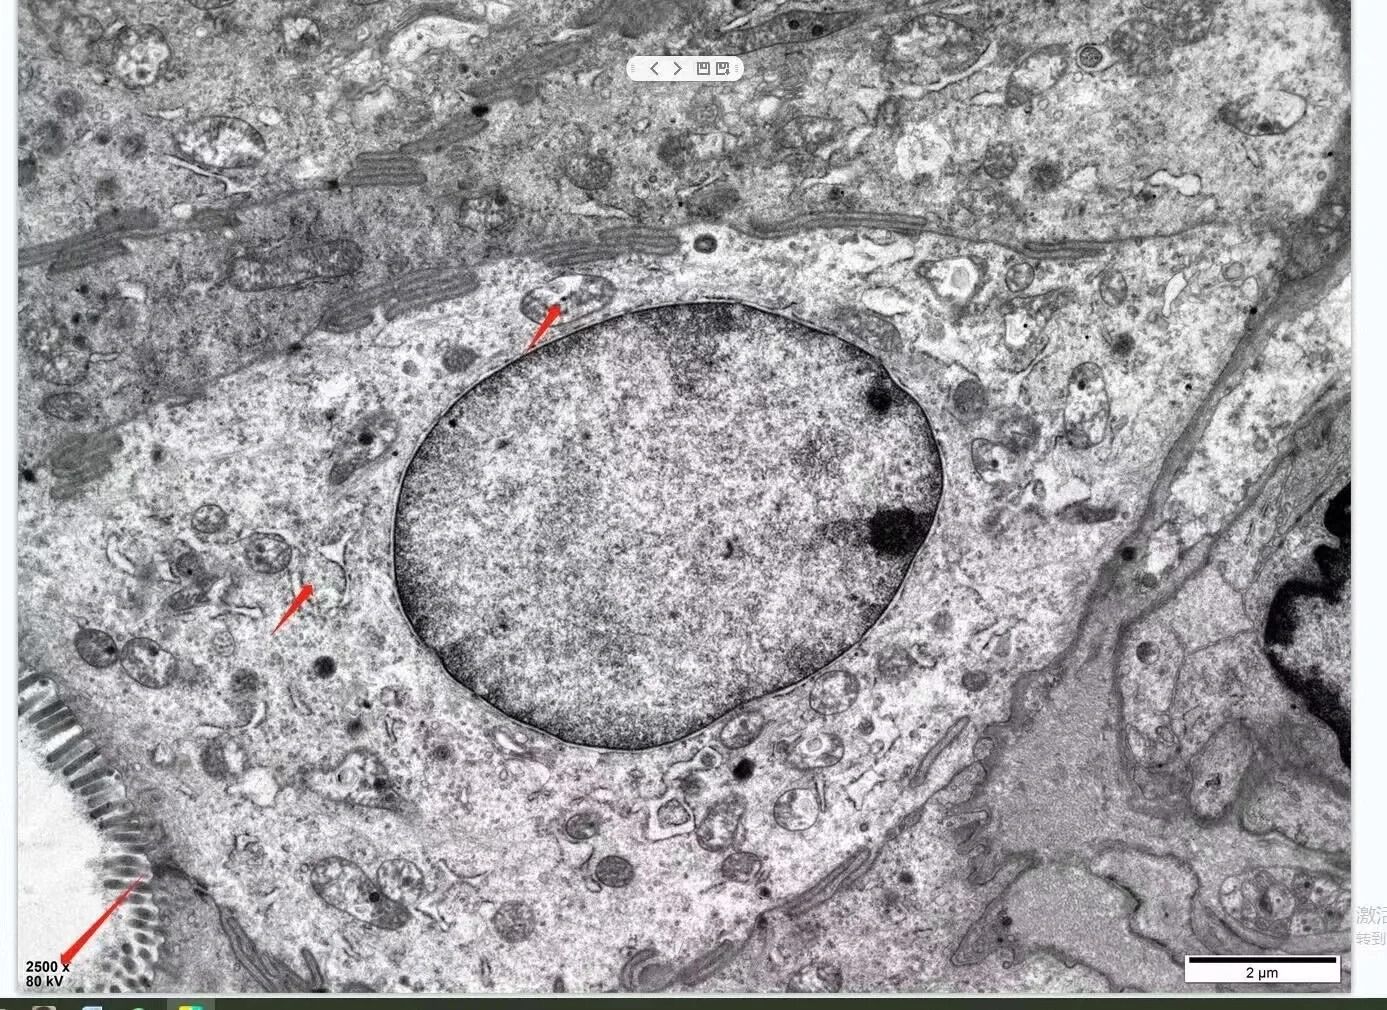

細胞結構

在獲取實驗數據時,我們可以選擇拍攝不同放大倍率的圖像,以觀察樣品的形貌和內部結構。此外,通過調整TEM的衍射鏡,我們還可以獲得樣品的電子衍射圖,用于分析樣品的晶體結構和晶相組成。